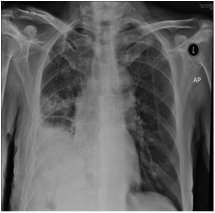

For the index admission, the patient was initially presented with fever and cough with sputum for 2 days. Physical examination found decrease air-entry in the right lower chest; heart sounds were normal; the abdomen was soft with a surgical scar in the right frank. CXR showed opacity in right lower zone (picture 1),but the diagnostic chest tap did not yield any fluid. He was managed as a case of chest infection and was started on Augmentin. Blood test showed a normochromic normocytic anaemia (9.7), the CEA (Carcinoembryonic antigen) was markedly elevated (84). Sputum grew E.coli. His fever subsided and he was then discharged home with CT scan of thorax and colonoscopy arranged. The patient was admitted six weeks later for one day history of fresh mouthful haemoptysis. He also complained of persistent cough and on-going weight loss since last admission. Sputum grew ESBL E.coli. He was given Cravit only in view of stable clinical condition. On the day after completion of antibiotic, the patient was admitted again for fever and purulent sputum. CXR did not show any significant interval change. This time sputum grew commensals only, but in view of the persistent symptoms and recent positive sputum culture, he was put on Ertapenem. However, 2 weeks later, he was admitted again for haemoptysis. Respiratory team was consulted for the unresolved pneumonia.

The team assessed the patient and reviewed all his medical history. This patient had repeated positive growth of ESBL E.coli from the respiratory tract which is uncommon cause of community acquired pneumonia. Moreover, the unresolved pneumonia might be related to the history of intra-abdominal operation which resulted in damage of the thoracic-abdominal barrier. The history of lung shadow also suggested a long existing lung problem. Therefore, we advanced the appointment of the CT scan of thorax and abdomen. (Picture 2) CT showed empyema necessitates in the right lower thorax with extension through the diaphragm and involvement of the abdominal wall. Finding was suggestive of long standing infection with disruption of the thoracic-abdominal barrier due to previous surgery. Barium follow-through showed mucosal irregularity in the hepatic flexure without definite communication to the right pleural cavity.